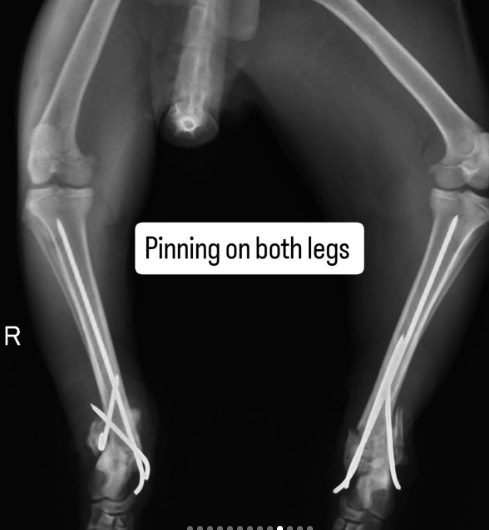

After going from pillar to post and getting no help, his feeder reached out to me. She had first aid done and was wondering what to do next as Timon needed urgent and intensive intervention. His bones were crushed and one was jutting out.

We got various opinions and decided to admit Timon at @petology_clinic where Timon underwent surgery yesterday.